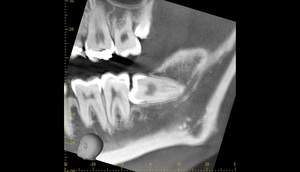

麻布十番歯科での右下の親知らずが真横に生えている症例のレントゲン写真

右下の親知らずが気になると言う主訴でいらっしゃった患者様です。

レントゲンで確認すると、真横にはえており、さらに、下歯槽神経と接触しているようにみえます。

根の形は先細りの形態ですので、抜くのはそこまで難しくないと思われます。根の形の最終確認と、下歯槽神経の位置確認のためにCTを撮影することにしました。